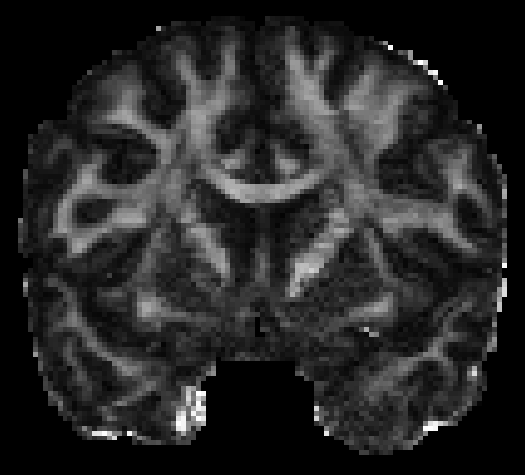

The visualization of inpainted results (showing the whole diffusion tensor for each voxel) generated from different models are demonstrated in Figure 3, where the tensor is represented in RGB coding that colours red, green and blue represent diffusion in the x, y, and z axes respectively. One typical example of reconstruction in the disrupted ROIs has been zoomed for visualization. Compared to the ground truth, TW-BAG is able to generate more distinct orientations following the original distribution and intensity across sagittal, coronal and axial views, which could demonstrate water diffusivity (denoted by eigenvalues of tensor model) more accurately. As indicated in Figure 4, the boundaries and textures of the FA map for TW-BAG are less blurry than the other competing models, validating the effectiveness of TW-BAG from a neuroscience perspective.

III-F Efficiency Study

| (a) Disrupted | (b) GT | (c) 32 | (d) 37 | (e) 42 | (f) 47 |